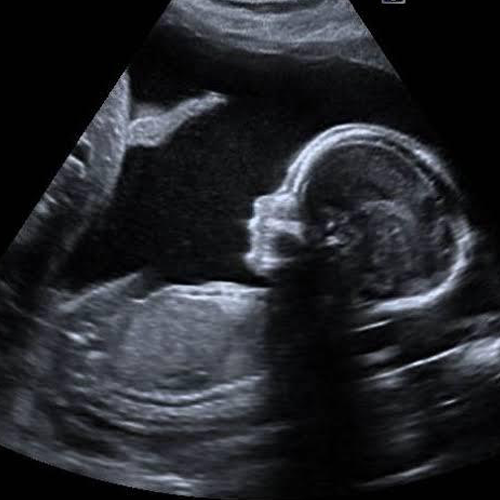

Best Scanning Center In Nakodar